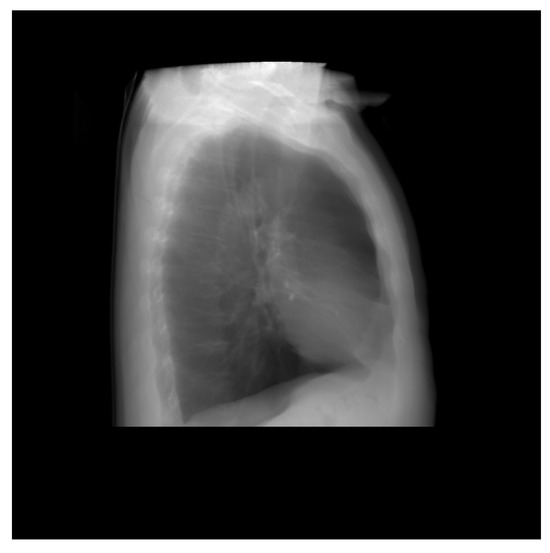

Thus, DRR is calculated by averaging the CT linear attenuation coefficient of the voxel along a ray from the virtual X-ray source to each pixel in the resultant image. DRR generation process is shown in Figure 4. However, in the segmented CT, the lung section’s CT number is 1, and 0 for the other section. Thus, averaging the intensity gives no effective result. For this, maximum intensity is considered along the ray. The Figure 5 and Figure 6 denote the PA and lateral view of the CT image respectively, and Figure 7 and Figure 8 denote corresponding segmented DRR.

Figure 6.

Lateral view of the DRR image.

Figure 7.

Posteroanterior(PA) view of the segmented DRR image.

Figure 8.

Lateral view of the segmented DRR image.